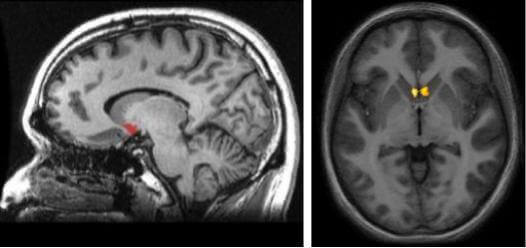

Si nos preguntamos ahora dónde se encuentra esta estructura, deberemos visualizar por un momento un área subcortical (debajo del cortex) justo en una zona de interconexión entre el núcleo caudado, el putamen y el septum. Así, lo más interesante sobre el núcleo accumbens y su localización, es el hecho de que forma parte de la vía dopaminérgica en el cerebro. Se trata de la llamada vía mesolímbica, encargada de estimularnos cada vez que nuestro cerebro entiende que estamos llevando a cabo experiencias positivas y gratificantes.

Cada hemisferio cerebral tiene su núcleo accumbens. De este modo, el sistema de recompensa orquestado por la dopamina llega a cada área del cerebro. Estamos a su vez ante una estructura que forma parte de los llamados ganglios basales. Así, y aunque a simple vista y mediante las imágenes nos pueda parecer más bien pequeño, lo que más la caracteriza al núcleo accumbens es su gran conectividad.